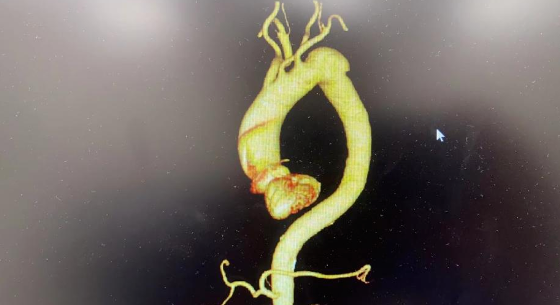

11月28日,一位八旬老汉来到四川泰康医院就诊,主诉胸痛,心外科周宏主任详细问诊后,患者2019年在外院曾诊断主动脉夹层形成却未行特殊治疗;结合患者胸痛症状,周宏主任建议立即收治入院行主动脉CTA检查,结果如周宏主任所料,患者主动脉CTA提示左锁骨下动脉开口外侧0.5cm处见一主动脉瘤,患者竟揣着这颗不定时炸弹生活了4年!

四川泰康医院心外科遂启动全院MDT,邀请放射科、超声科、麻醉科、ICU、手术室等相关科室共同讨论,由于患者主动脉瘤与左锁骨下动脉开口距离仅0.5cm,最终制订主动脉覆膜支架腔内隔绝术+预开窗,备左锁骨下动脉-左颈总动脉搭桥术。

转机!四川泰康医院顺利“拆弹”

12月5日经过缜密的准备,手术顺利进行,经过3小时的奋战,周宏主任通过预开窗方法利用覆膜支架顺利将主动脉瘤隔绝并保留左锁骨下动脉,成功将患者保留4年的定时炸弹拆除。患者术后返回ICU,周宏主任全程于病床前守护,于夜间顺利脱机拔管,安稳恢复。

据了解,主动脉瘤指主动脉壁局部或弥漫性的异常扩张,超过正常血管直径的 50%,向外膨出形成的血管“瘤”。随着主动脉瘤体长大会出现疼痛等周围组织及神经压迫症状,甚至破裂。急性主动脉瘤破裂十分凶险,可能危及生命。常发生在升主动脉主动脉弓、胸部降主动脉、胸腹主动脉和腹主动脉。